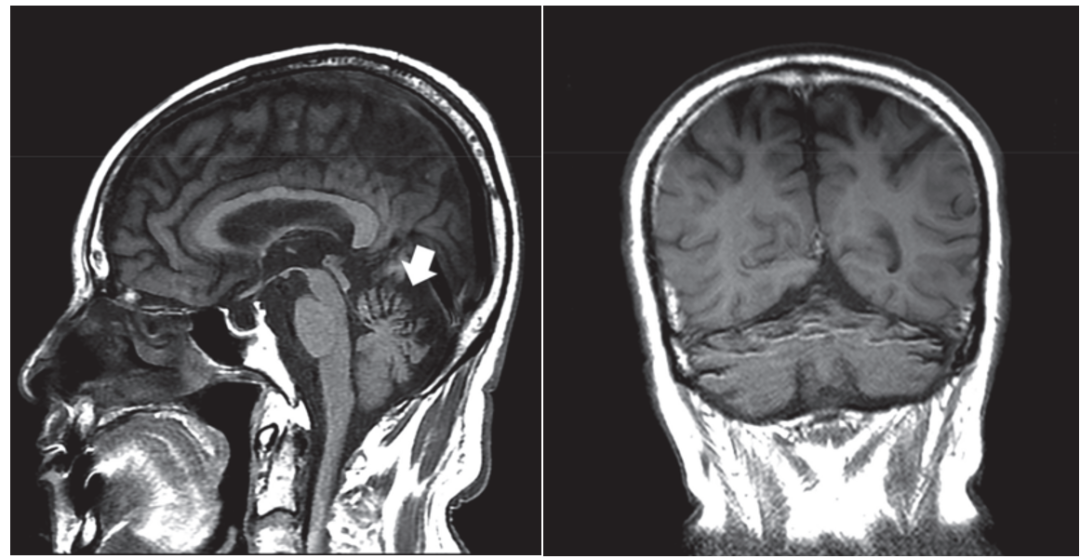

桥脑中央髓鞘溶解

这是渗透性脱髓鞘综合征中的一种类型,属于脑桥基底部的急性髓鞘溶解性病变,多见于快速纠正低钠血症和酒精中毒。组织病理学上是一种非炎症性脱髓鞘,而神经元和相关轴突相对保留,伴少突胶质细胞数量减少和巨噬细胞浸润。病灶呈现“蝙蝠翅”征、“三叉戟”征或“猪鼻”征。

颅脑MRI示:脑桥基底部T1WI低信号

T2WI和FLAIR高信号

病灶呈对称分布

“蝙蝠翅”征 “三叉戟”征 “猪鼻”征

小脑变性

以小脑蚓部萎缩为主,环池、小脑上池、枕大池扩大,可合并大脑萎缩,主要的病理改变为小脑蚓部皮质变性。临床表现为共济失调、眼球震颤、言语缓慢、行走不稳。

颅脑MRI示小脑萎缩

尤其是在小脑蚓部和半球的的前部